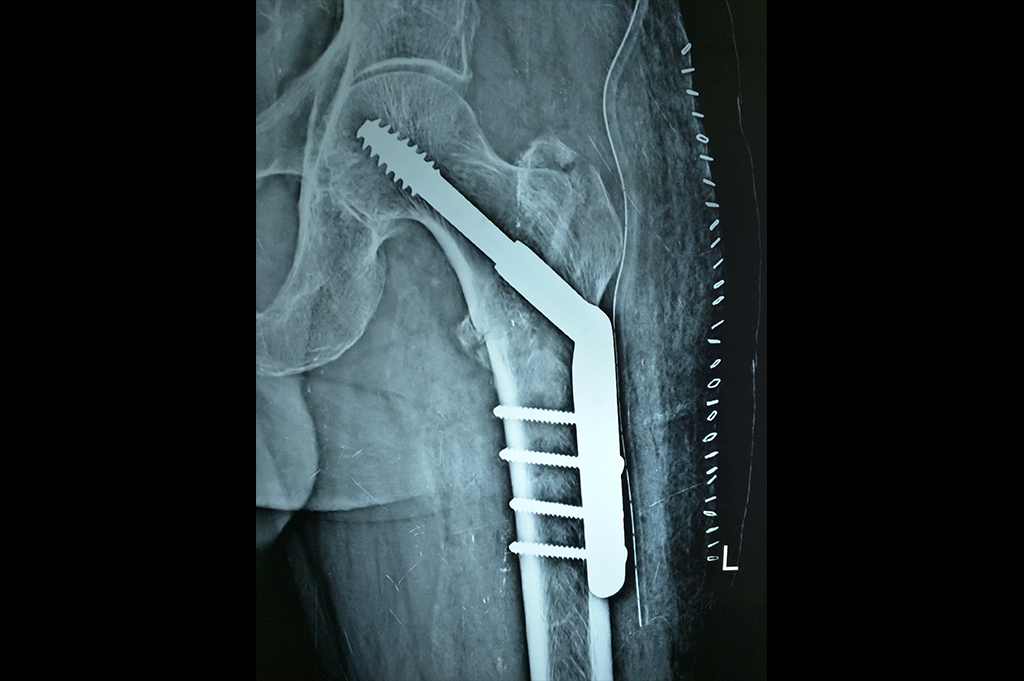

Subtrochanteric Fracture